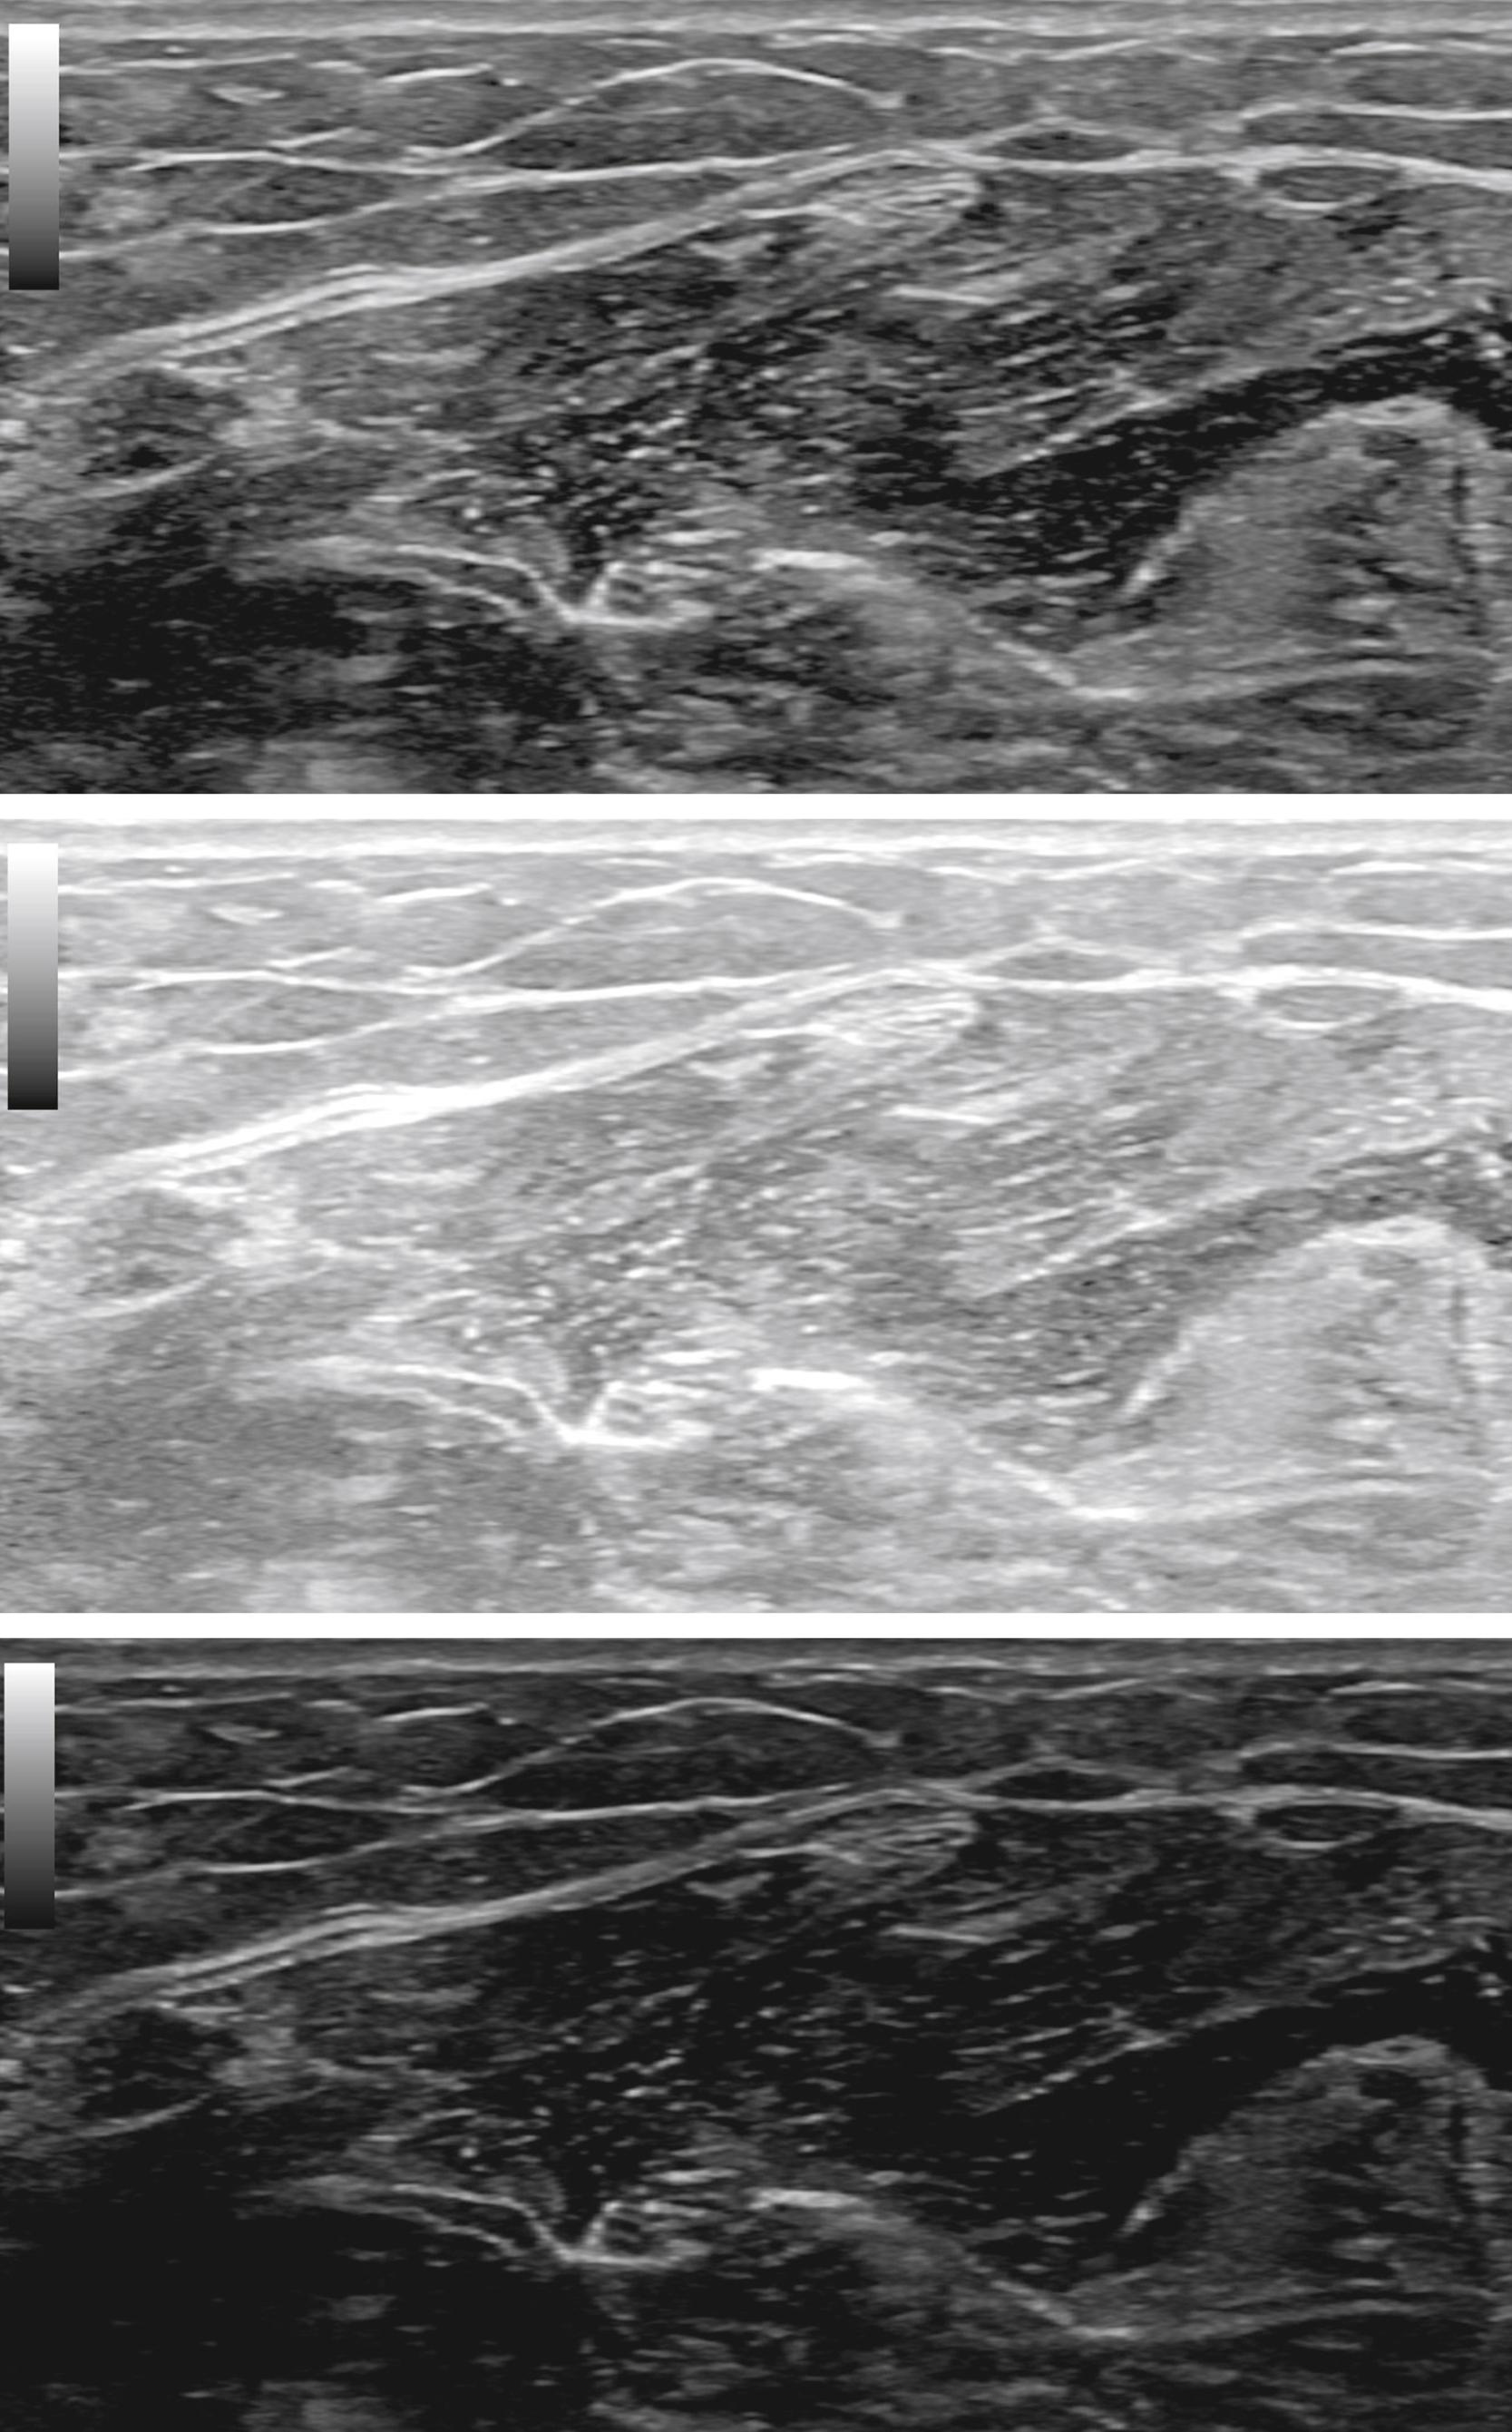

To obtain an ultrasound image, the first step is to set the depth. If the depth is set too deep, much of the image will be taken up by black areas below the area of interest where the ultrasound beam has been completely attenuated ( Fig. 17.9 , top image). If the depth is set too shallow, one may unintentionally cut off part of the object of interest and its surrounding structures below ( Fig. 17.9 , bottom image). The second step is to adjust the ultrasound focus ( Fig. 17.10 ). Similar to a camera, the ultrasound machine can focus the sound waves at a particular depth, called the focal depth, to best see images at that depth. The focal depth is adjustable on all ultrasound machines. Indeed, one can set more than one focal depth. However, the downside of setting increased numbers of focal depths is that it decreases the frame rate (the rate at which the image refreshes itself). Slower frame rates result in blurring of the image as the probe is moved. The third major adjustment is the brightness ( Fig. 17.11 ), which is basically an adjustment of gain or sensitivity. The brightness setting does not change the power of the ultrasound waves sent out, but more or less amplifies the returning echoes. The brightness setting should be adjusted so that the image is neither washed out nor too dark such that important details cannot be seen. The fourth adjustment is the frequency. The highest frequency will result in the best resolution. However, the higher the frequency, the more attenuation of the ultrasound beam as it moves deeper. If deeper structures are not well seen, one should either change the probe to a lower-frequency probe or lower the frequency of the probe being used until the deeper structures of interest are well seen. All commercial medical ultrasound machines come with presets for all parameters, which are already optimized depending on which structures are being viewed (e.g., wrist, ankle, etc.). These preset settings are an excellent starting point and often will need little to no adjustment for the most common studies done.

Fig. 17.9, Depth setting.

Fig. 17.10, Focal points.

Fig. 17.11, Brightness adjustment.